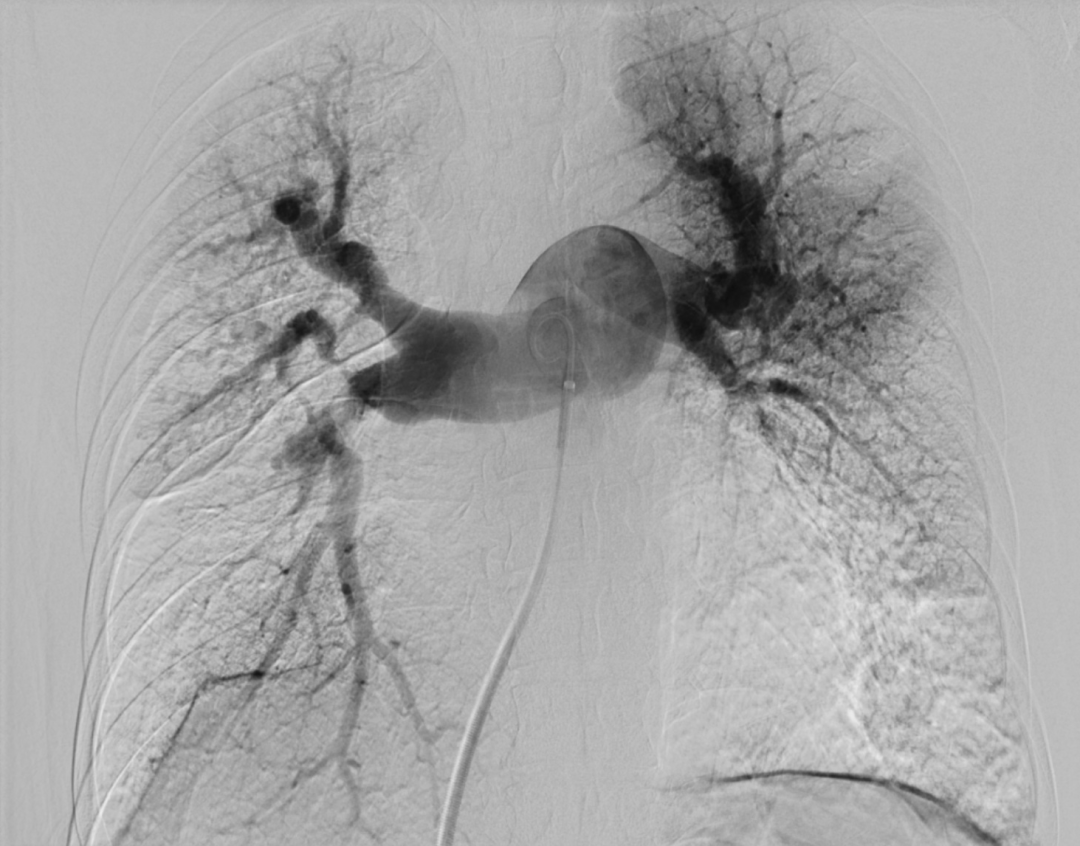

肺动脉造影:右肺上叶前段、后段肺动脉,中叶肺动脉、基底干肺动脉重度狭窄,尖段肺动脉迂曲扩张;左肺下叶肺动脉次全闭塞。

第二次(2020.9)因咯血入我院,查NT-proBNP 1760pg/ml,2020-09-21行支气管动脉栓塞术,2020-09-23右心导管检查:肺动脉压70/27(41)mmHg,PVR 16.1WU,对左肺舌段和基底干肺动脉行球囊扩张治疗。

第四次(2021.7)拟行肺动脉支架植入术入院,于2021-7-7行右心导管检查+肺动脉造影+肺动脉支架植入术:支架植入前测量右房压为25/9(15)mmHg,右心室压为55/2(19)mmHg,肺动脉压为55/29(38)mmHg,CO 2.2 L/min,PVR 11.8WU。测量左肺下叶肺动脉近端压力51/23(32)mmHg,远端压力为15/11(12)mmHg,右肺下叶肺动脉近端压力52/20(31)mmHg,远端压力为11/8(9)mmHg,于右肺动脉基底干狭窄处植入PLU-STENT M30支架一枚,测量病变远端压力为51/23(32)mmHg,未见明显压差。

术前肺动脉造影